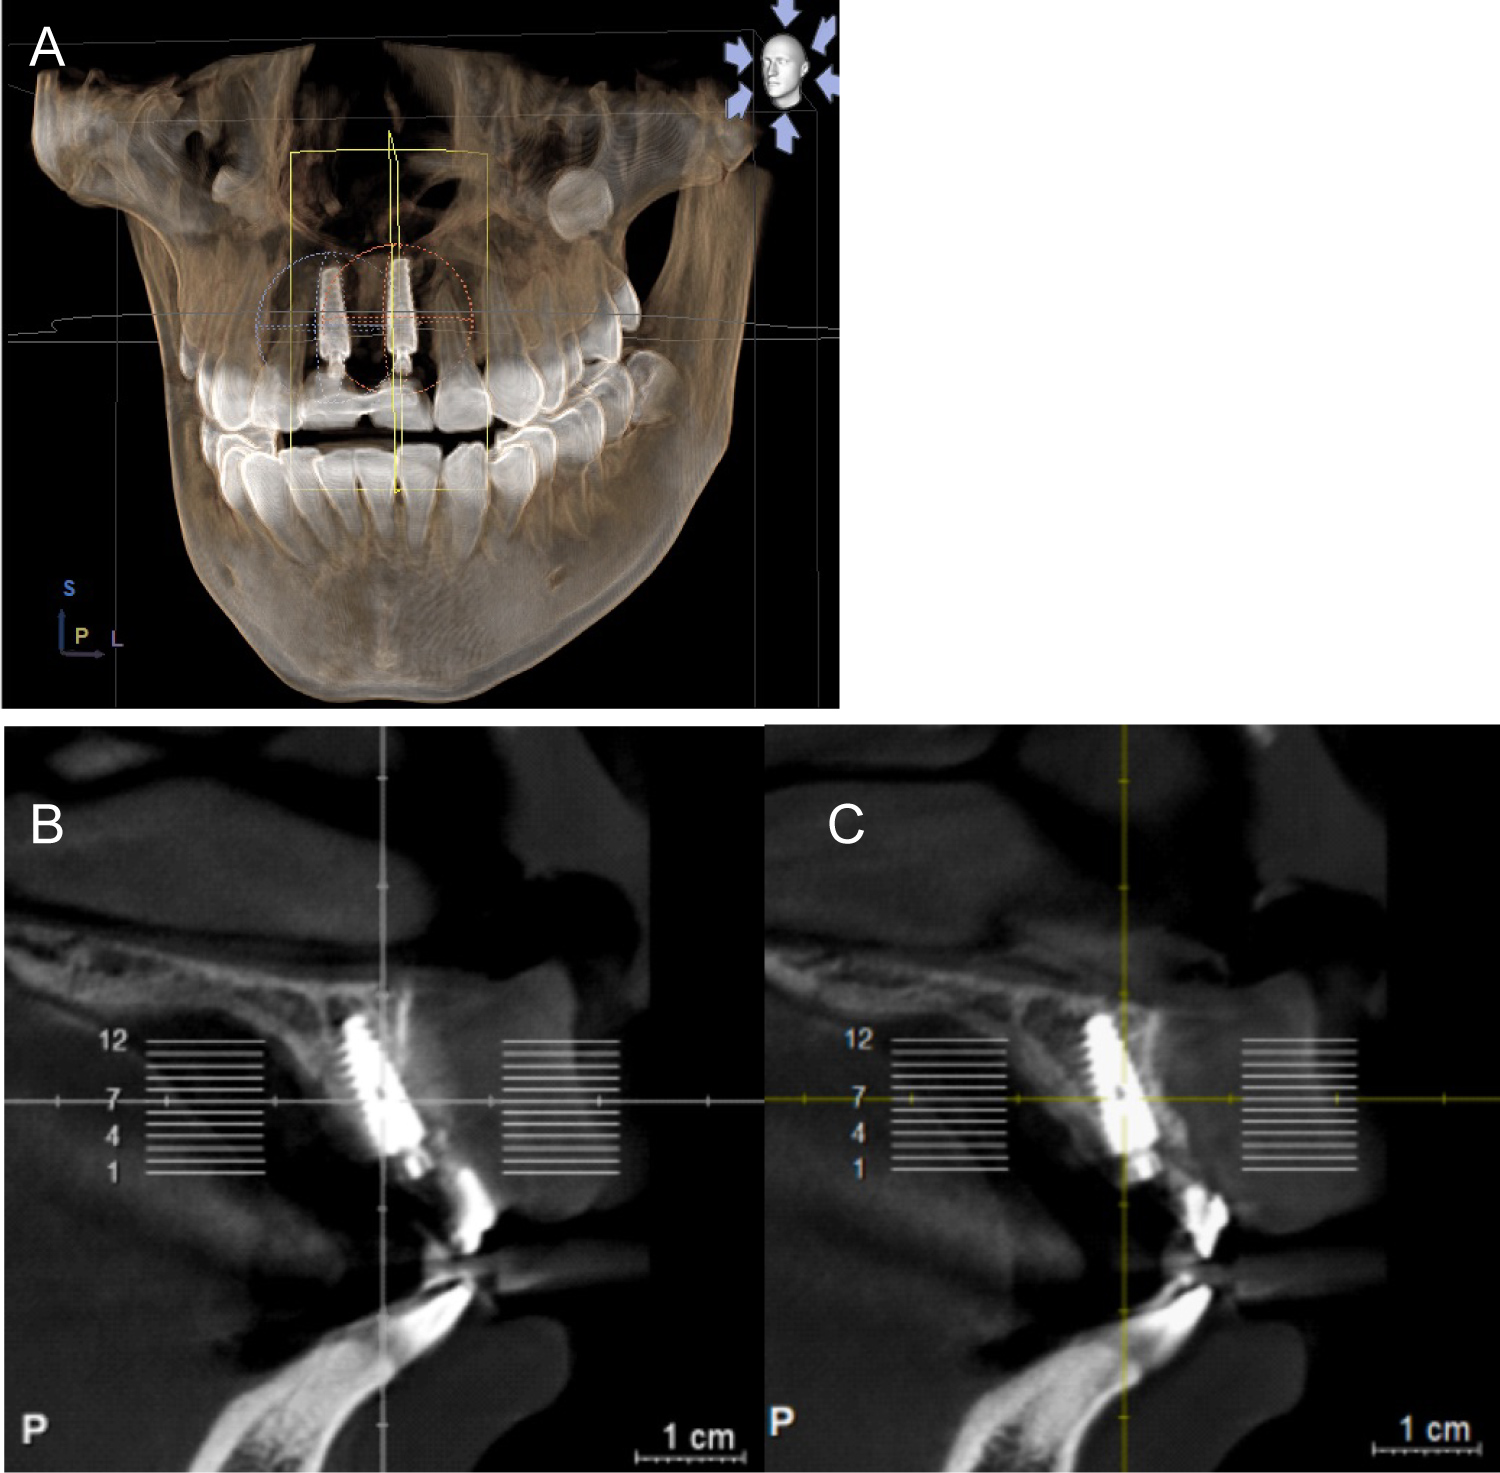

Before final restorations, follow up CBCT scans were instructed for implant assessment and their relation within the anterior maxillary ridge (Figure 8).

Figure 8: (A) Volumetric CBCT; (B) Sagittal view implant right incisor; (C) Sagittal view implant left incisor. View Figure 8